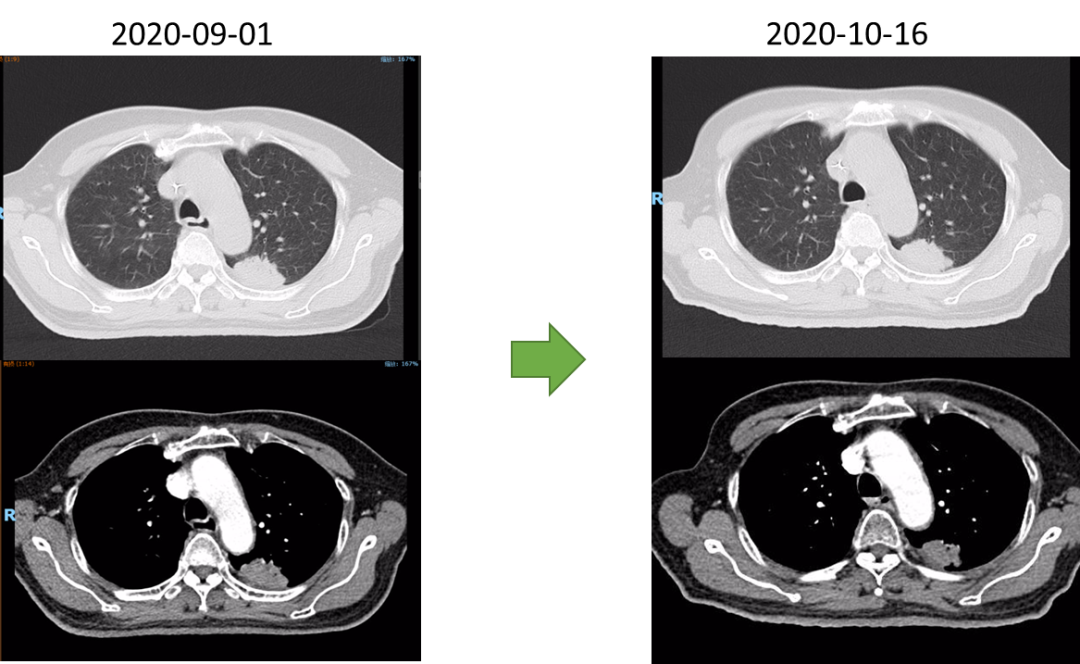

放射治疗结束复查胸部CT:左肺上叶尖后段与左肺下叶背段交界处病灶较前略显缩小,现最大横断面约2.6*2.8厘米,边缘可见毛刺,增强后可见强化,邻近胸膜稍增厚。食道中段管壁增厚,上下累及约4.5厘米(约胸5/6椎间隙水平至胸8椎体上缘水平),增强后强化程度似较前有所减低,隆突下见境界不清淋巴结。

2021-10-28外院PET-CT:原食管胸下段管壁高代谢灶较前缩小,放射性较前减低,现大小约15×17×17mm,SUVmax 3.1,考虑为治疗后改变。左肺上叶团块状高代谢灶较前缩小,放射性摄取较前减低,现大小约25×18mm,SUVmax 2.1,考虑为治疗后改变。

2022-03-28 PET-CT:1、食管癌放化疗后,食管胸中段管壁不规则增厚伴结节状代谢增高,与上次(2021-10-28)PET/CT检查对比,病灶代谢较前明显增高,考虑为肿瘤复发病灶。2、左肺癌放疗后及靶向药治疗后,原左肺上叶团块状高代谢“肿瘤灶”,现范围较前稍缩小,代谢较前稍减低,考虑为治疗后改变(肿瘤完全活性受抑,伴少许炎性反应可能)。